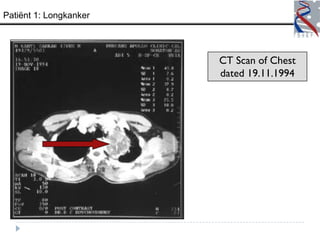

Patiënt 1: Longkanker

CT Scan of Chest

dated 19.11.1994

– CT scan v.d borst (11/19/94) - 8 x 6.4 cm massa boven in mediastinum

Patiënt 1: Longkanker CT Scan of Chest dated 19.11.1994